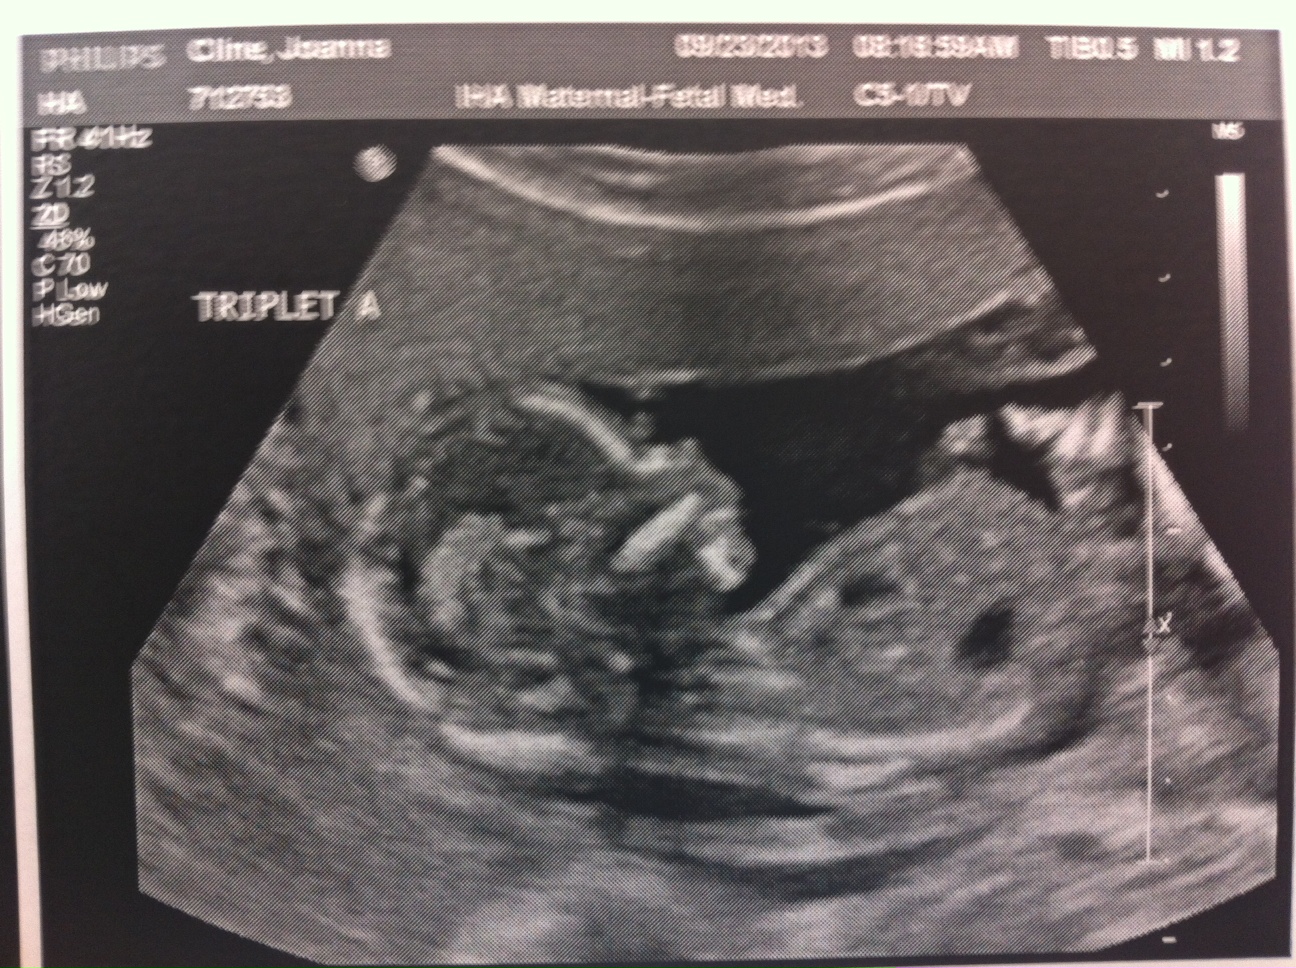

Baby A – is a BOY!

A is 170 grams, B is 175 grams and C is 178 grams so they’re all measuring well. Grow, grow, grow!